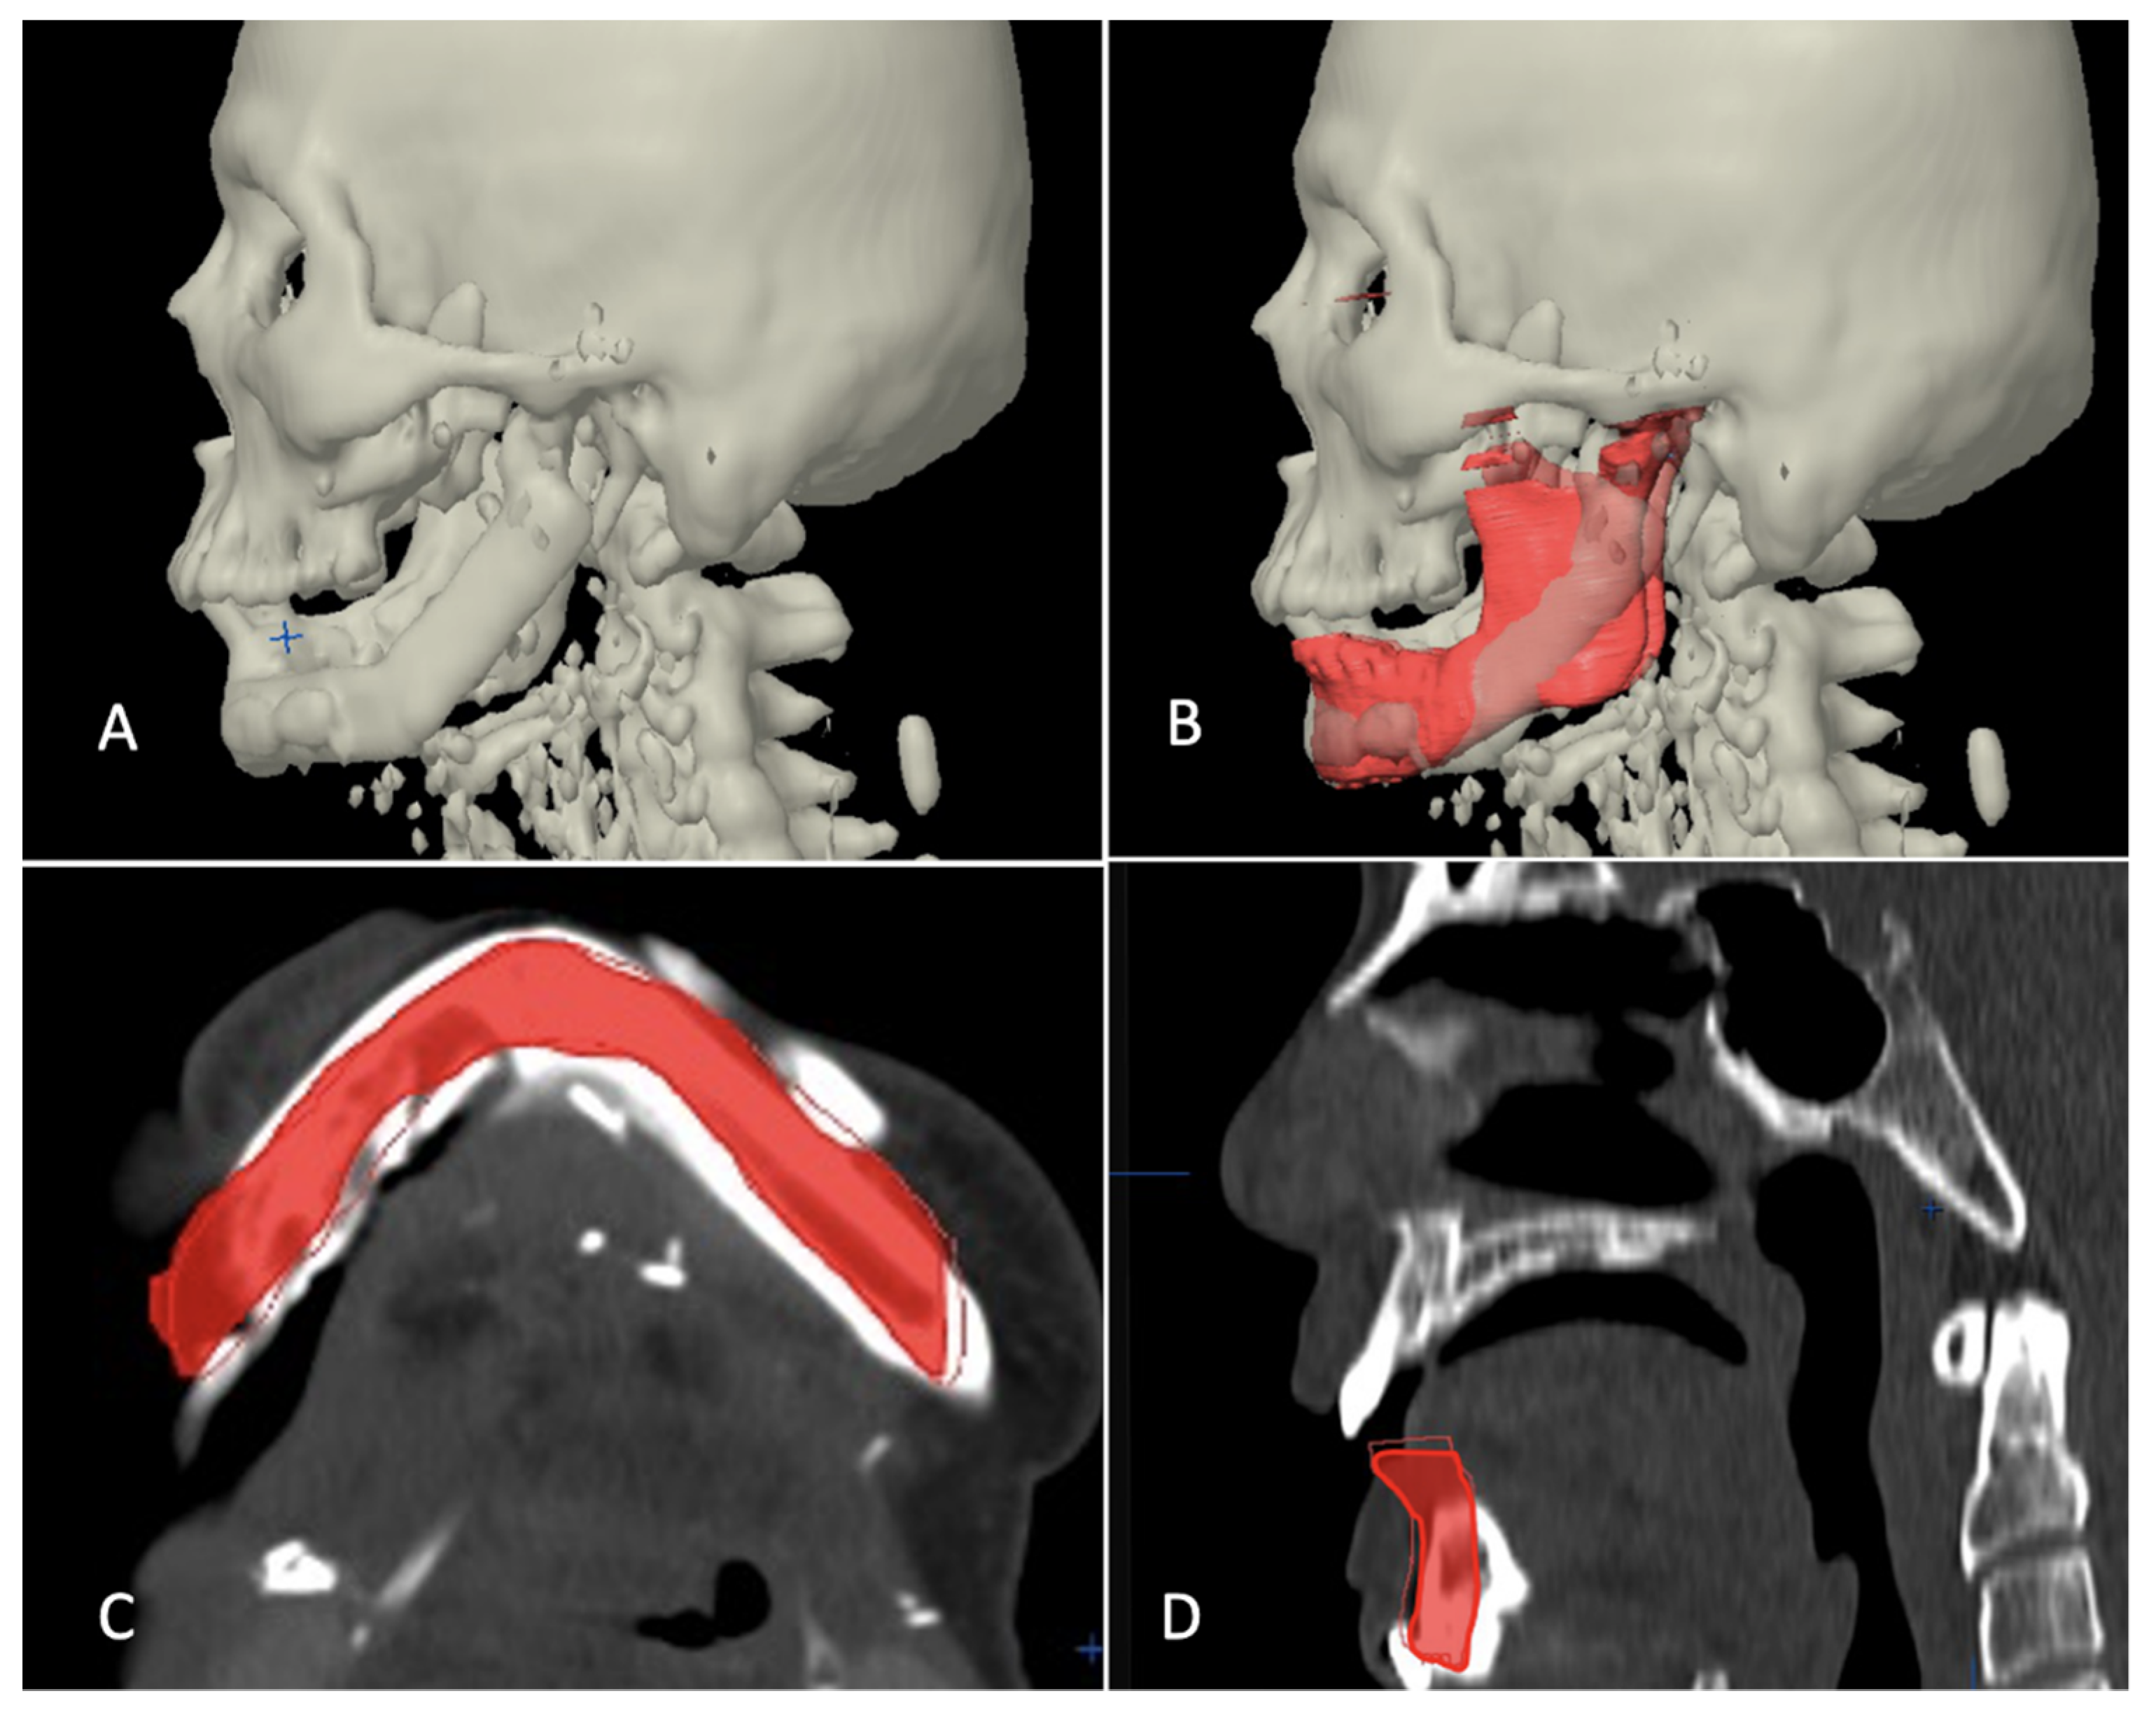

2.4. Evaluation of Accuracy of Planning

The evaluation phase in postoperative period started with a repeat CT scan after six months of reconstructive surgery and involved superimposition of postoperative images with virtually reconstructed mandible in the computer planning (Figure 8, Figure 9 and Figure 10). The 3D craniofacial image was reoriented with counterclockwise pitch rotation to allow the whole mandible from the right to the left angle be seen in one axial 2D view. In the 2D view, a section through the mid-way of chin and parallel to the lower mandibular border was selected for measurement (Figure 11A). The entire length was divided into ten segments, each separated with an angulation of eighteen degrees from the base line joining the two angles, resulting into 11 points of measurement (Figure 11B). The linear discrepancies between virtually planned position and the buccal aspect of actual bone position were measured. The mean differences in the distance and the standard deviation were consequently calculated. The differences in mean between the three categories were also calculated to compare the accuracy of reconstruction.

Figure 11.

Evaluation of accuracy of reconstruction with virtual plan. (A) Reconstructed mandible superimposed over virtual plan, a section through the mid-way of chin and parallel to the lower mandibular border selected for measurement (yellow line). (B) The length of reconstruction divided into ten segments by eleven red lines, eighteen degrees each from center of angle-angle baseline and discrepancy measured at eleven points at the outer border (excluding the reconstruction plate).